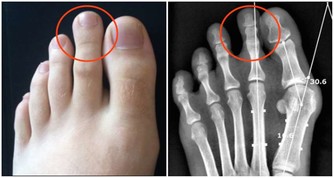

好發的部位是皮膚油脂分泌最少的小腿前側以及腰部附近。